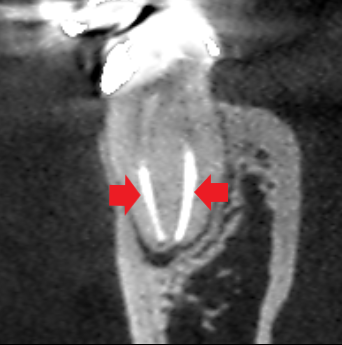

実際に「根管」の画像をご覧頂きましょう。歯の中にある黒い筋が根管です。